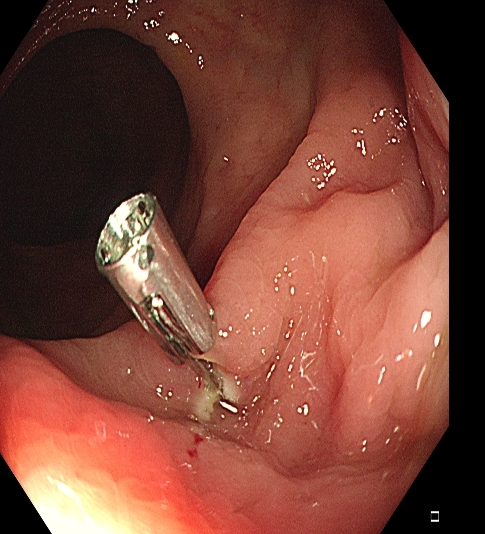

操作过程中应夹住息肉头端,适当上提(可避免损伤肌层),与肠壁保持适当距离,当息肉蒂部出现发白时,停止电凝,钳除病变。应注意是,切除息肉不易过大,否则会造成通电时间延长,增加全层损伤的风险(图1)。

图1 热活检钳除术示意图,A 钳除前,B 钳除后创面。C-D:热活检钳除术注意事项,息肉体积过大,增加电凝时间,造成透壁性损伤。